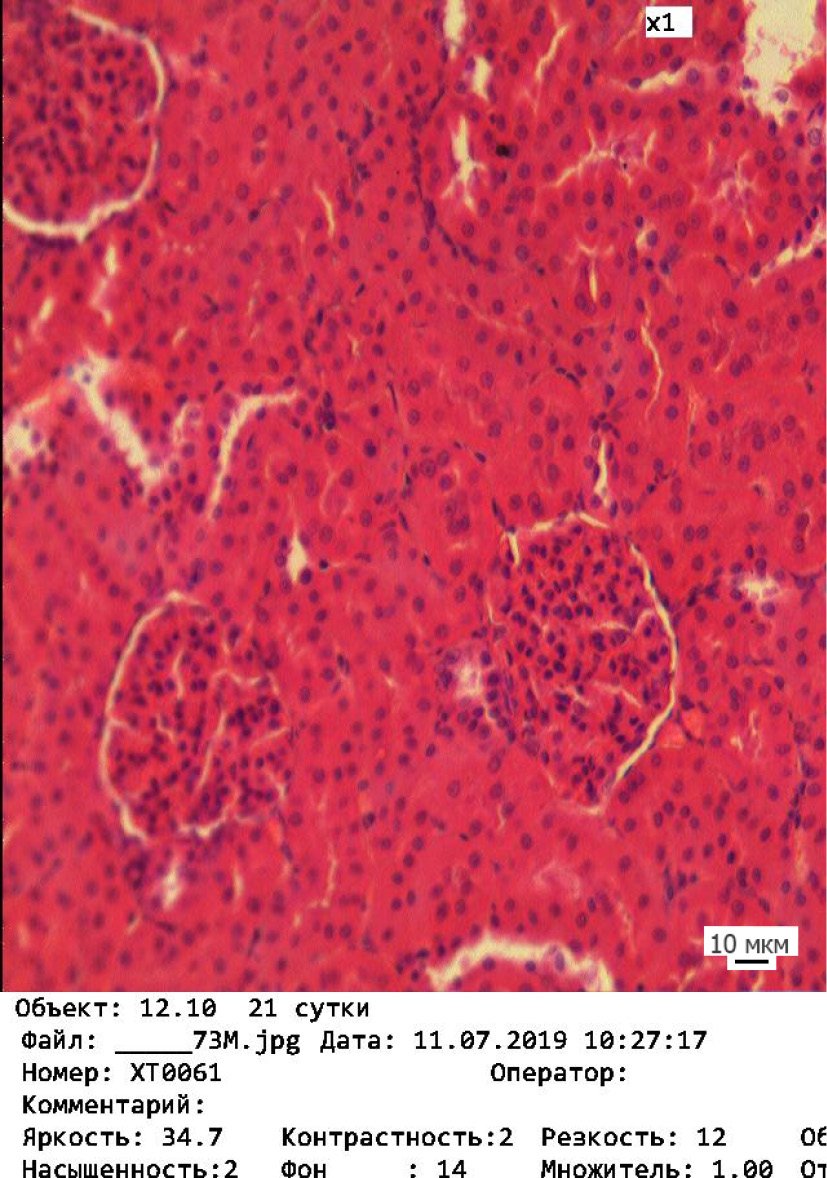

Изменения произошли во всех трёх экспериментальных группах. В ткани почек подопытных групп наблюдались патоморфологические изменения различной степени. Происходит нарушение как функциональных, так и компенсаторных механизмов. Визуально у животных 1-й подопытной группы отмечается значительная сегментация клубочков и дистрофические изменения в канальцах почек (рис. 1). Во 2-й подопытной группе происходит более выраженная сегментация клубочков и появление очагов клеточной инфильтрации (рис. 2). В канальцах регистрируются локальные признаки дистрофических и некротических изменений – исчезновение ядер и нарушение чётких границ между клетками. В ткани почек животных 3-й подопытной группы отмечаются признаки склерозирования, которые проявляются в уменьшении размеров почечного тельца (рис. 3). Чётко визуализируется нарушение канальцевого аппарата – нарастание дистрофических изменений и слущивание эпителия канальцев.

Рис. 3. Корковое вещество почки у животных 3-й подопытной группы. Окраска гематоксилином – эозином. Об. 20 / Fig. 3. Cortical substance of the kidney of the animals in the experimental group three. Stained with hematoxylin and eosin. Magn. ×20